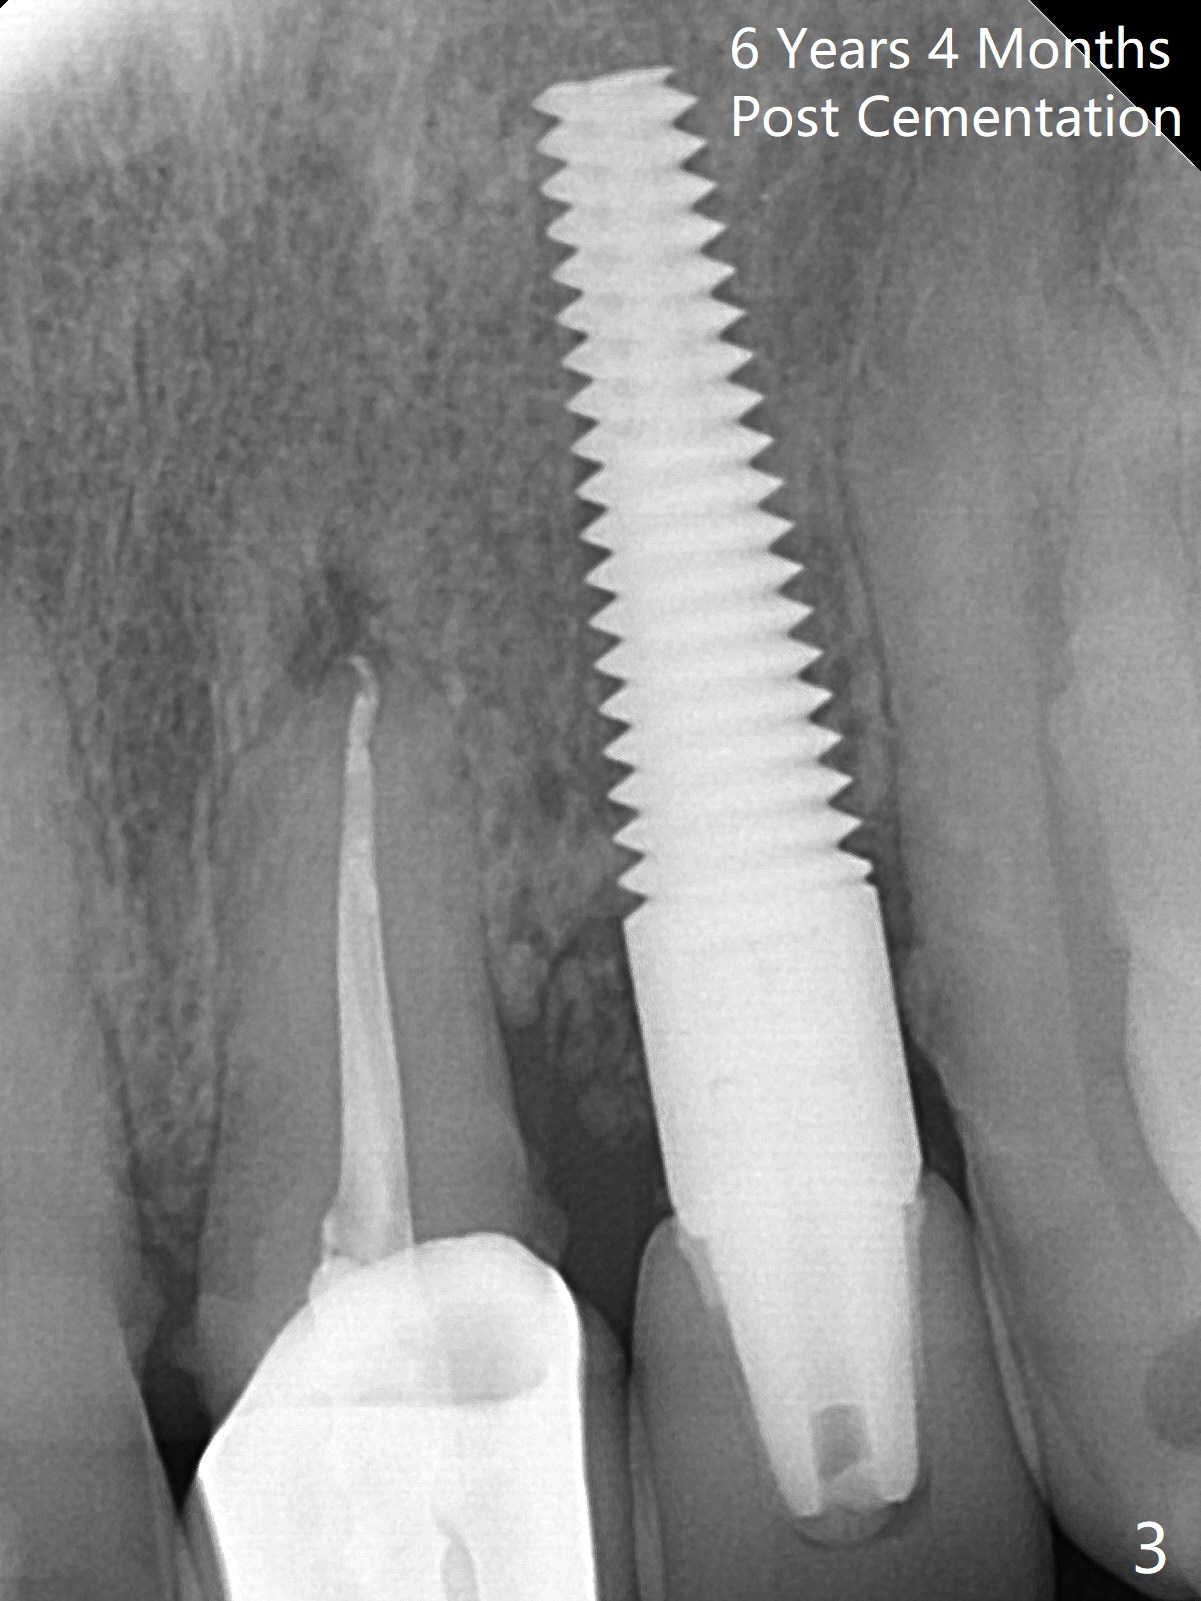

59岁女,口腔卫生差,害怕治疗,左上侧切牙即种牙冠粘固后6年4个月,同意深洗(图三)。虽然软硬组织没有特殊变化,再细点植体可能更好些(图一,二)。